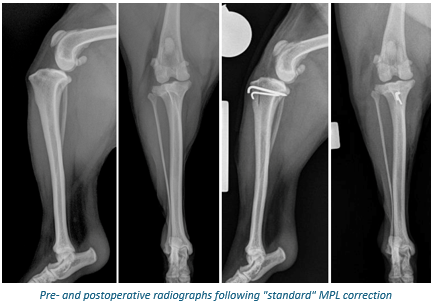

Surgical correction of MPL is recommended for all dogs with grade 3 or 4 disease and many dogs with grade 2 disease. The type of surgical correction is dependent on the nature and degree of deformity present in each dog which is measured from a preoperative patellar tracking CT. In most dogs with grade 2 or 3 disease, a so-called “standard” approach with four main components is performed:

• The trochlear groove is deepened to capture the patella (block recession trochleoplasty)

• The insertion of the patella tendon onto the tibia is moved laterally to align the patella with the trochlear groove (tibial tuberosity transposition)

• The soft tissues on the outside aspect of the leg are tightened (lateral fascial imbrication)

• The soft tissues on the inside aspect of the leg are released (medial desmotomy)